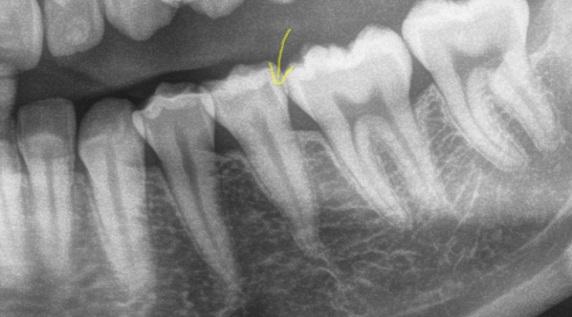

Befund: versteckte Zwischenraum-Caries am Backenzahn

unsichtbare<br />

Zwischenraum-Caries

unsichtbare